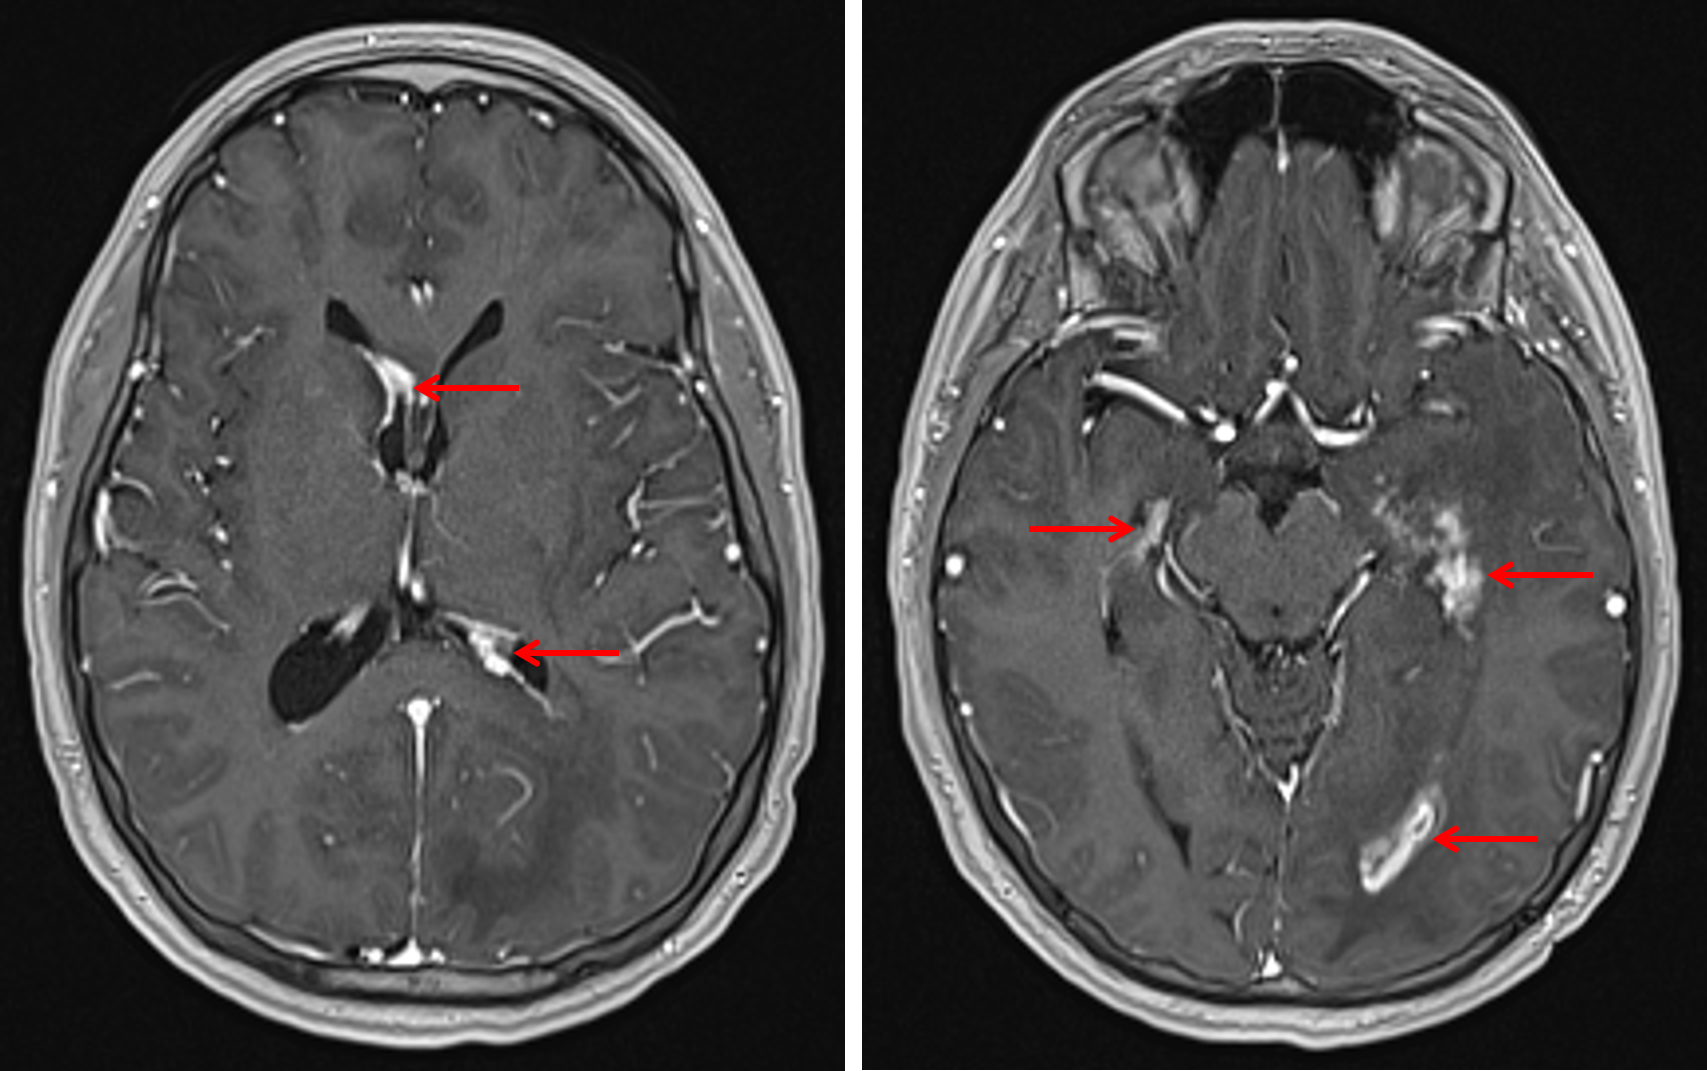

Neurosarcoidosis